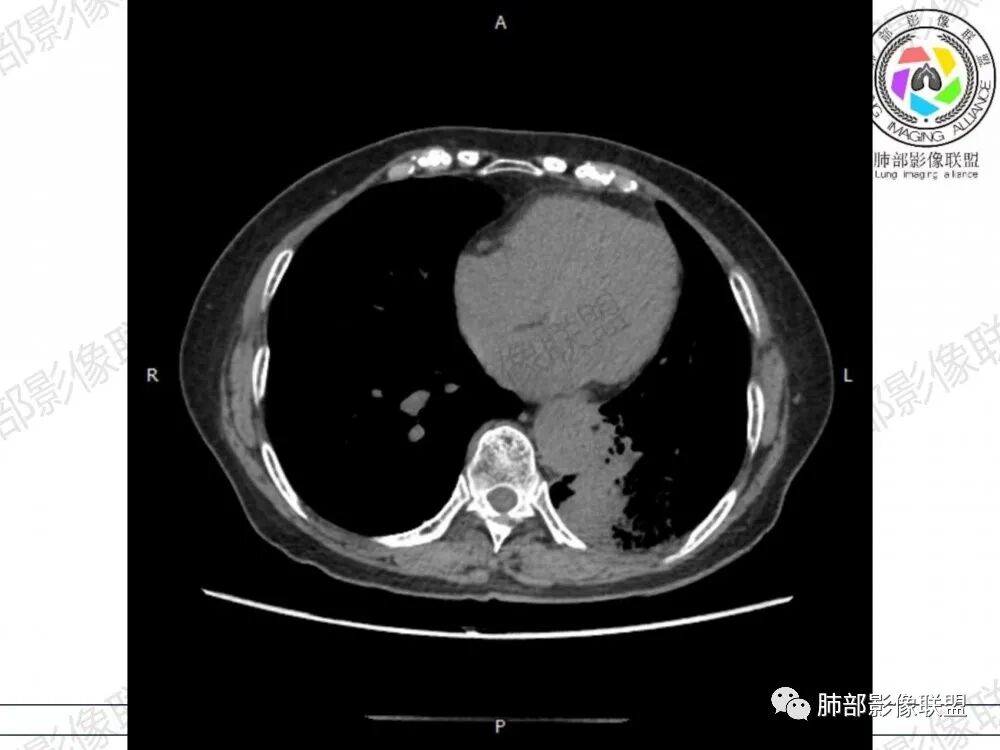

2、影像表现:无肺气肿背景,病变定位于左肺下叶背内侧基底段,病灶呈不规则团块影,靠近胸膜侧,其内密度不均匀,内见空洞、实变及磨玻璃影,磨玻璃影呈碎石路征,边界清楚,实性肿块边界膨隆,其内见空洞。空洞周围比较实。病灶较大的支气管通畅,细小的支气管成“枯枝征”。无胸膜增厚及胸膜腔积液,增强扫描呈中度强化,见血管造影征。

3、 由于粘液重力作用,粘液腺癌易发生于下肺胸膜下,由于小叶间隔阻挡,胸膜侵犯少,通常是胸膜与周围肺组织的模糊增厚,粘液腺癌的胸膜侧较宽,但胸水少见也是诊断特点之一。

2、肺淋巴瘤:CT表现:两肺多发实变,多伴有空气支气管征,空泡征、磨玻璃密度、肺叶局部实变、小叶间隔增厚、气管壁增厚、增强见血管造影征,与本病有重叠,由于粘液腺癌有重力作用、粘液腺癌易发生于下肺胸膜下有助于鉴别。